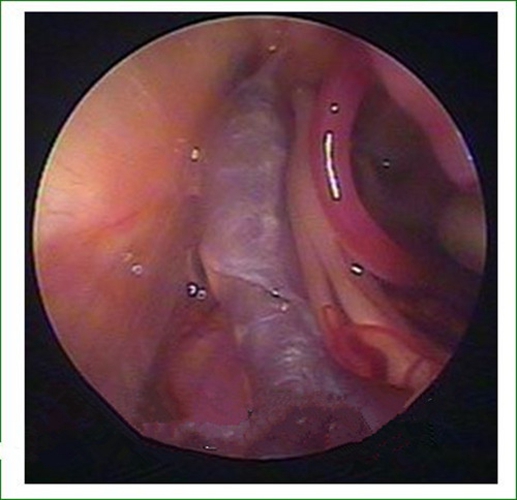

治療三叉神經痛

微創治療三叉神經痛的